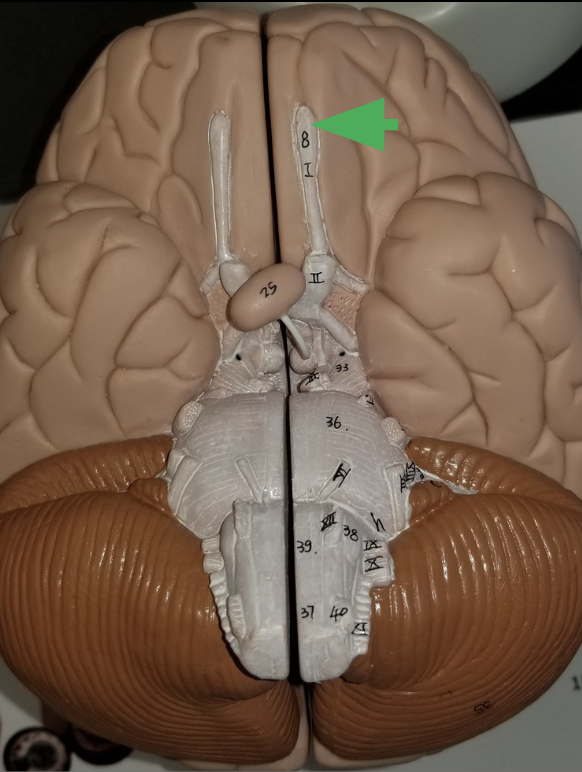

What is the arrow indicating?

1 of the 2 cerebral hemispheres

what is the arrow pointing at?

Vermis

Nervous tissue between both cerebellar hemispheres

what does the arrow indicate?

Olfactory bulb

What is the function of an olfactory bulb?

Receives input from olfactory neurons coming from nasal cavity

Olfactory Track

What does the olfactory tract do?

carries information from the olfactory to the cerebrum, where it can be sorted, interpreted, and processes

Optic Nerve (cranial nerve 2)

What does the optic nerve do?

carries axons from retina of the eye

what does the arrow indicate ?

Optic chiasm

What happens in the optic chiasm?

where some axons in each optic nerve cross over to the other side

What does the arrow indicate?

Optic Track

What does the optic track do?

carry axons from optic nerves ro the thalamus

What is the arrow pointing at?

Oculomotor nerve

What is the arrow indicating?

Trigeminal nerve (cranial nerve 5 /V )

What does the trigeminal nerve do?

Carries sensory information from the face

Carries motor commands to chewing muscles